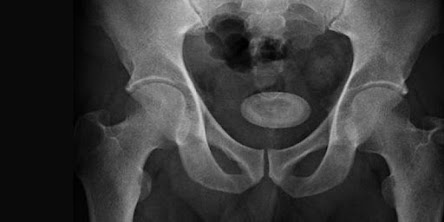

They are frequently discovered when a person undergoes an X-ray for another medical condition. Larger bladder stones may require removal by medical professionals. Sometimes a single stone will form, and other times a cluster of stones may.

X-ray